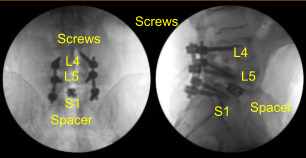

The patient was draped sterilely. Intraoperative CT scan was obtained and the data was transferred to the neuronavigation computer. Accuracy was verified and neuronavigation techniques were used to place pedicle screws in the L4, L5, and S1 pedicles bilaterally.

We began decorticating with an electric high-speed drill and Leksell rongeur, cannulated the pedicles of L4 bilaterally with the navigated pedicle finder, palpated for breaches and measured the depths. We used a 5.0-mm tap and placed 6.0 x 45 mm titanium pedicle screws using navigation without difficulty.

Next, we placed the bilateral S1 pedicle screws in the same manner using neuronavigation techniques. Four starting points and trajectory identification, cannulation of the sacrum, we palpated, we under tapped by 2-mm using 5.0 tap and then we placed 7 mm x 40 mm screws without difficulty. Neuromonitoring signals were stable. We did not put the L5 screws at this point.

The interspace was irrigated clear. Morselized autograft was packed in the interspace, and then a titanium 22-mm long expandable interbody spacer was gently tamped into the interspace with a mallet. AP and lateral fluoroscopy was performed to confirm midline positioning and depth; the cage was expanded to the appropriate tightness and tight.

X-rays were repeated to confirm correct positioning and size. Neuromonitoring signals were stable. Next with the left L5 pedicle completely isolated and exposed, we placed left L5 pedicle screw decorticating with electric high-speed drill cannulating with the curved freehand Lenke pedicle finder palpating for breaches using 5.0 mm tap and placing 45 mm x 6.0 diameter titanium pedicle screw without difficulty.

We then similarly placed a right L5 pedicle screw as well using similar technique. We draped the patient sterilely and obtained an intraoperative CT scan which showed correct positioning of all the pedicle screws and interbody spacer.

Precut and precontoured titanium rods were selected and placed across the tulips and secured with locking caps, which were all final tightened with torquing and anti-torque devices at L4, L5 and S1. Morselized demineralized bone matrix autograft collected from the decompression as well as bone morphogenic protein allograft were packed into the lateral gutters from L4 to S1 to the posterolateral arthrodesis.

We took final AP and lateral x-rays, which showed correct positioning of all the hardware. The closure will be dictated separately. At the end of the case, the patient was turned supine on the cart, and transported to the recovery room in stable condition.